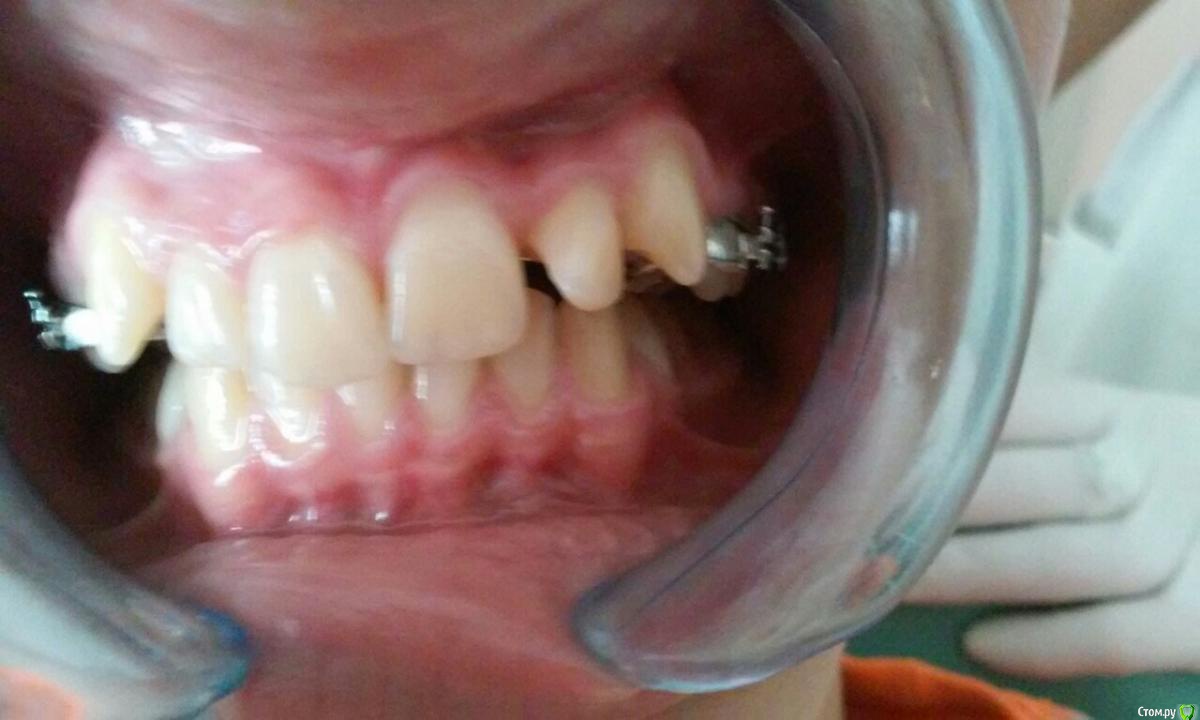

natkoorth1991 Опубликовано 28 августа, 2015 Поделиться Опубликовано 28 августа, 2015 мальчик, 13 лет, премоляры удалять не хотели, поставила хайракс на в / ч- получила перекрестную окклюзию. Извините за плохие фото( Что теперь делать? фото после: Ссылка на комментарий

Molox Опубликовано 29 августа, 2015 Поделиться Опубликовано 29 августа, 2015 Выведете. Наверх поставьте зауженную дугу, на низ - стандартную или широкую. Поскольку диастемы не появилось, у меня стойкое подозрение, что расширение было зубоальвеолярным, значит на брекетах вернуть все можно. Скажите, а зачем вообще аппарат ставили? Дефицит места минимальный, десна хорошая; на брекетах за 6 мес все бы расправилось. Ссылка на комментарий

Yana guapa Опубликовано 29 августа, 2015 Поделиться Опубликовано 29 августа, 2015 конечно, показаний для PRE здесь не было. но раз уж поставили, то поставили.Я бы теперь скручила винт в обратную сторону. будет нужный результат. Потом сняла бы аппарат и просто сделала бы перерыв. Премоляры сами немного вернуться к исходному положению Нет ТРГ. Но стакой инклинацией верхних центральных резцов могу предположить, что НЧ смещена кзади. Если это выяснится, и в ходе лечения НЧ будем перемещать вперед, то это тоже поспособствует лучшему смыканию. ждем снимков 2 1 Ссылка на комментарий

natkoorth1991 Опубликовано 29 августа, 2015 Автор Поделиться Опубликовано 29 августа, 2015 брекеты на вч не ставить пока? или зафиксировать и раскручивать обратно. По моделям там есть смещение нч где-то на половину бугра. На трг отправлю. Ссылка на комментарий